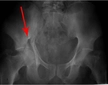

4. Tanı ve Tedavi YöntemleriPelvis bölgesi ağrısının tanısı, hastanın öyküsü, fiziksel muayene ve gerekirse görüntüleme yöntemleri (ultrason, MR vb.) ile konulmaktadır. Tedavi yöntemleri ise ağrının nedenine bağlı olarak değişkenlik göstermektedir. Genel tedavi seçenekleri şunlardır: